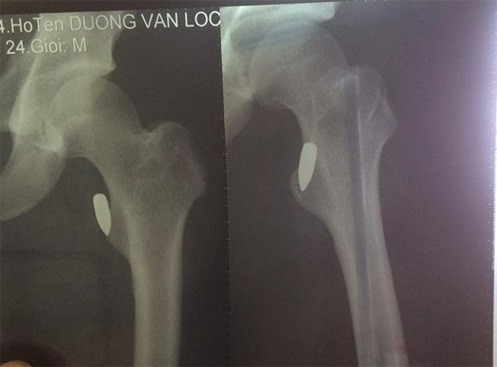

Trước đó, trưa 26/9, Dương Văn Lộc (24 tuổi, vận động viên Pencak silat tỉnh Vĩnh Phúc) sau buổi tập cùng với đội tuyển đã cùng người bạn tên Thiện lấy xe máy đi uống nước. Vừa đi qua ngã tư chợ Tổng (TP Vĩnh Yên) thì Lộc nghe thấy tiếng nổ, sau đó đùi anh đau buốt và chảy máu nhiều nên phải đưa đi viện cấp cứu.

Hình chụp vết thương của nạn nhân. Ảnh: CTV

Bác sĩ chẩn đoán trong đùi anh Lộc có viên đạn. Vì vết thương khá phức tạp nên sau khi sơ cứu, anh Lộc được chuyển xuống Bệnh viện Việt Đức (Hà Nội). Tổn thương do đạn gây ra khá phức tạp nên các bác sĩ vẫn chưa thể gắp đầu đạn ra ngoài.